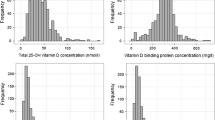

Seasonal variations in serum 25(OH)D: blood donors

The CIE-weighted UV radiation increased from 0.36 Wh/m2 in December to 24.25 Wh/m2 in July and was positively correlated with serum 25(OH)D (r S = 0.333; p < 0.001) Great variations were found in the mean concentrations of 25(OH)D during the different months of the year (Table 2 and Fig. 1). The mean serum concentration of 25(OH)D was 73 % higher in July (81.9 ± 26.2 nmol/L) than in February (47.4 ± 20.7 nmol/L), (p < 0.001). The mean serum concentration of 25(OH)D during the third quarter of the year (July to September, 77.7 ± 27.3 nmol/L) was 62 % higher than during the first quarter of the year (January–March, 47.9 ± 19.6 nmol/L), (p < 0.001).

During the first quarter of the year (January–March), 58.3 % (70/120) had serum concentrations of 25(OH)D lower than 50 nmol/L, and 87.5 % (105/120) had levels lower than 75 nmol/L, compared with the third quarter of the year (July–September), when 11.3 % (18/160) had levels below 50 nmol/L and 50 % (80/160) had levels below 75 nmol/L (p < 0.001) (Table 2 and Fig. 2).

Intra-individual variations in serum 25(OH)D during different seasons of the year: results from the thrombocyte donors

The mean serum concentrations of 25(OH)D followed the intensity of the UV light irradiance in the Gothenburg area and peaked in July, whereafter they decreased. The mean increase in serum 25(OH)D from April to August was 0.268 nmol/L/day (95 % CI 0.239–0.298 nmol/L/day) or 8.0 nmol/L/month (Fig. 3). The individual minimum and maximum serum levels of 25(OH)D in the study subjects were strongly correlated (r S = 0.684; p < 0.001), indicating that each individual follows his/her own curve. The intra-individual maximum change in serum 25(OH)D is shown in Table 4.